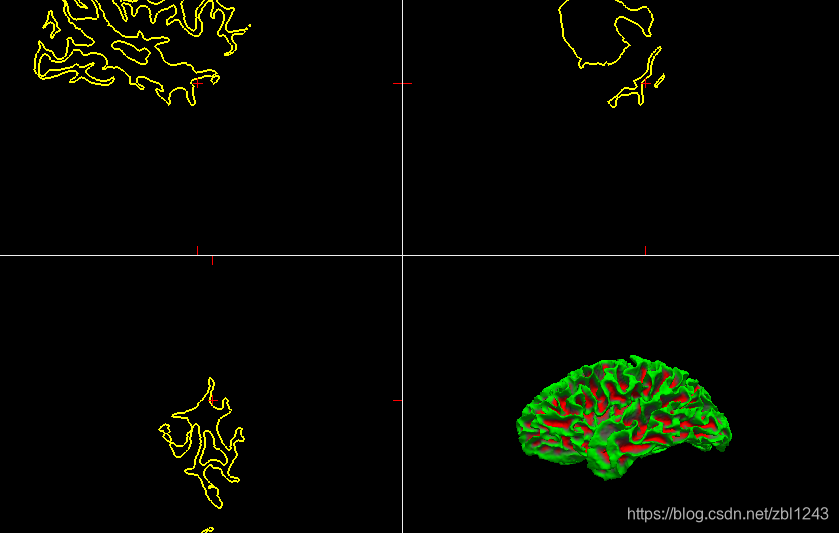

lh.white:

.pial加上文件夹中annot: